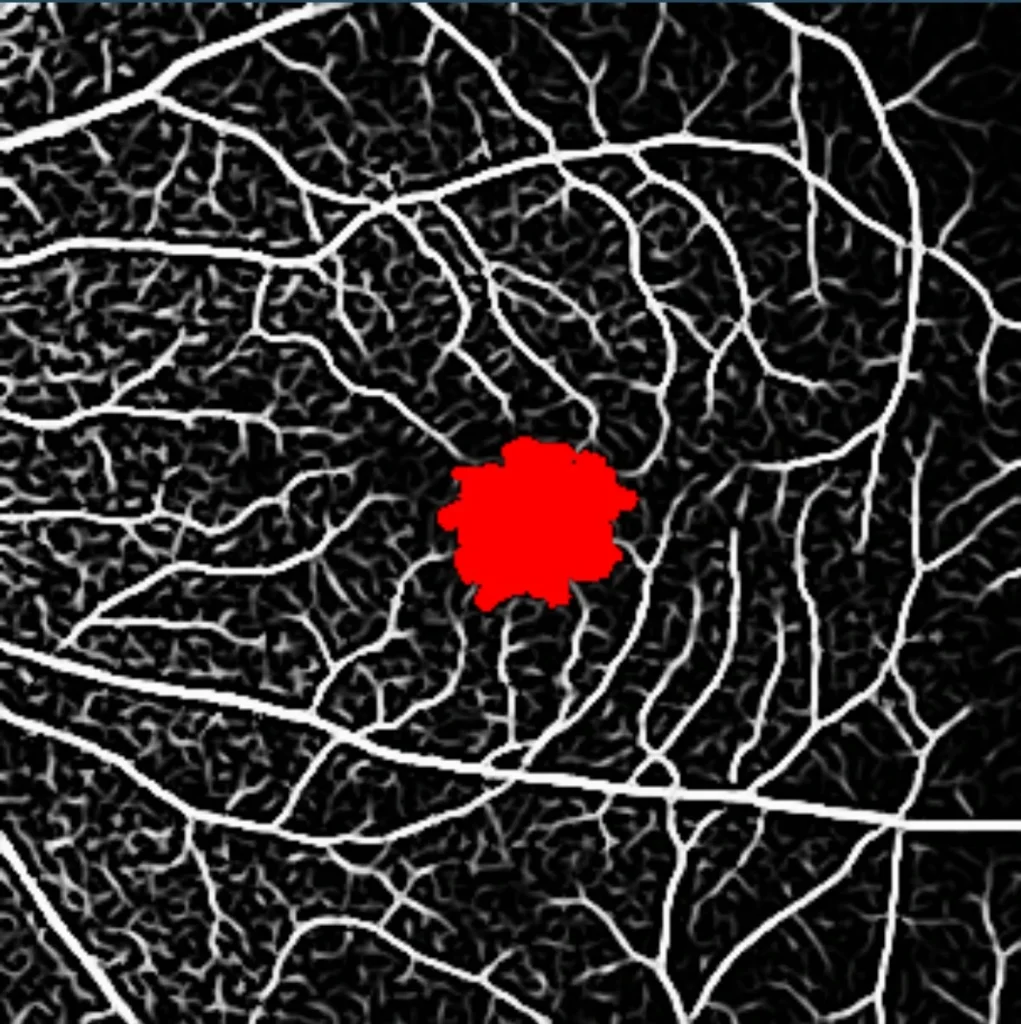

- OCT – Angiography (OCT-A)

We combine advanced imaging technologies with AI-driven analysis to accelerate biomarker discovery in ophthalmology. By integrating imaging modalities with biomolecular insights, we identify novel indicators of disease progression, treatment response, and patient-specific outcomes. Our AI capabilities refine and validate these biomarkers, unlocking the full potential of ophthalmic imaging to drive smarter, faster clinical trials. This includes advanced techniques such as:

Our multimodal overlays combine structural and functional imaging modalities, such as OCT, FAF, and microperimetry, to provide a more comprehensive understanding supported by expert-trained readers who interpret across modalities with deep disease insight.

Expanding Biomarker Capabilities

Voiant has built a robust and growing set of biomarkers to enhance trial outcomes, including:

- En Face Measurements